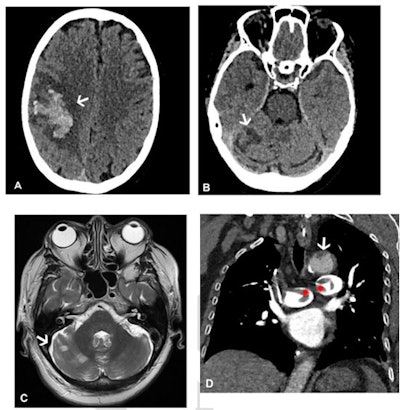

Images in a 64-year-old woman who presented with confusion and collapse and was diagnosed with intracranial hemorrhage associated with cerebral venous sinus thrombosis secondary to VITT. (A) Axial unenhanced head CT image demonstrates a large right parietal lobe intraparenchymal hemorrhage and (B) bilateral infarcts in the cerebellum confirmed on axial brain T2-weighted MRI. (D) CT pulmonary angiogram coronal reformatted image shows eccentric mural thrombus within the aorta (white arrow) and large central saddle embolus (red asterisks). Images and caption courtesy of the RSNA.Experts recommend symptom-specific imaging for VITT, but its prevalence remains unclear, Rogers and colleagues noted. To clarify the question, the group conducted a study that included 40 patients who developed thrombocytopenia after receiving their first dose of the AstraZeneca vaccine. The patients were imaged with CT, ultrasound, and/or MRI depending on protocol in seven different centers across the U.K.